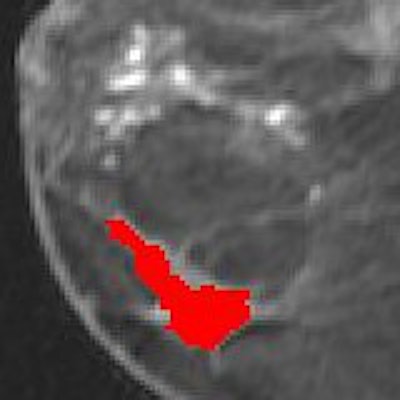

![]() |

| Morphological map generated by CADimas of invasive lobular breast carcinoma. Lesion is tagged as being highly suspicious. Image courtesy of Penn & Associates. |